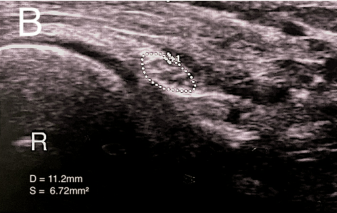

DOI: 10.7759/cureus.88503 아픈 오른쪽 팔의 신경은 (B) 무려 6.72mm²로 퉁퉁 부어있는 것을 발견했습니다. 근전도 검사에서는 보이지 않던 '신경 부종'과 '포착(눌림)'이 초음파 눈에는 딱 걸린 것이죠. * * * 4. 그래서 해결 방법은요? 이 환자를 어떻게 치료했을까요? 바로 '초음파 유도하 시술(Hydrodissection)' 입니다.